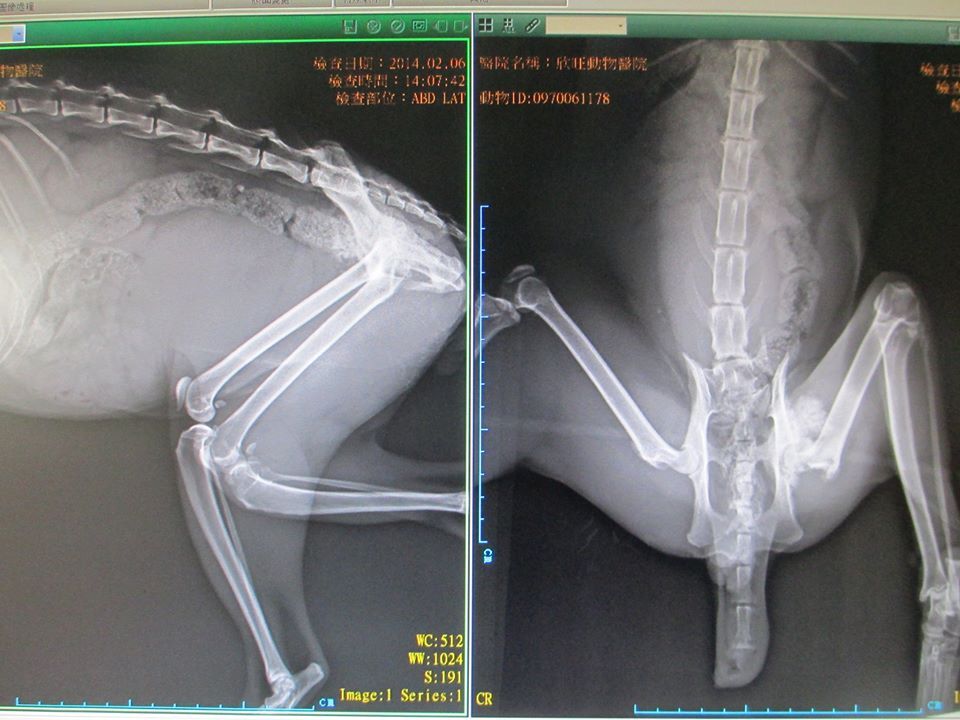

主題: 寒冬中的斷尾骨折小花 申請者姓名: 吳佩君 花色: 申請日期: 2014-03-17 13:30:01 申請者部落格: 申請者臉書網址: 所在縣市/合作醫院: 台北市/欣旺動物醫院 治療費用: 9800元 需求人數: 12人 已結案 (2014-05-18 09:40:36) 報名人員: Sunny Chen(已付款)、Forest(已付款)、grace0710(已付款)、megumi(已付款)、ERic YU(已付款)、Parry Hsu(已付款)、Queenie Chang(已付款)、clement(已付款)、豆腐人 x3(已付款)、小四(已付款)、 候補人員: 動物病情說明: 過年,對於我們是個喜慶的節日,對於斷尾的小花......卻沒有絲毫的歡喜

寒冬中忍受的斷尾骨折的疼痛,卑微的街貓們只能在人類的夾縫中生存,偏偏小花承受著不知是野狗咬傷或是街貓打架到潰爛見骨的疼痛與可能骨折的後腿,行動是如此的緩慢與笨拙,想見這過年他該如何躲避無情的鞭炮與飢餓??

或許是過度的驚嚇,可能是身體的痛楚,小花在誘捕籠中沒有一點掙扎與反抗,而是一種接受命運淬鍊的無奈與冷靜,也或許是身體的疼痛已經讓他沒有力氣反抗了。過年假期,中和地區的醫院並沒有營業,只得送往松山的欣旺動物醫院。空氣中濕潤的微雨更諷刺著年節的氣氛。小花終於見到了活下去的希望。

醫生稍事檢查,只能確定優先處理斷尾的傷口,視情況治療後腿(骨折OR拉傷),而且小花並未剪耳,所以節紮是勢在必行的了。